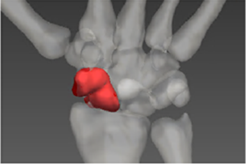

新冠大考,勇担社会责任。新冠疫情期间,团队率先投入科技战疫,在国际上首次实现感染肺三维重建模型,开发的AR远程指导系统投入火神山、雷神山等医院,成果被二十多家主流媒体专题报道,有效降低医源性交叉感染近万余次。

(图为 感染肺三维重建模型)